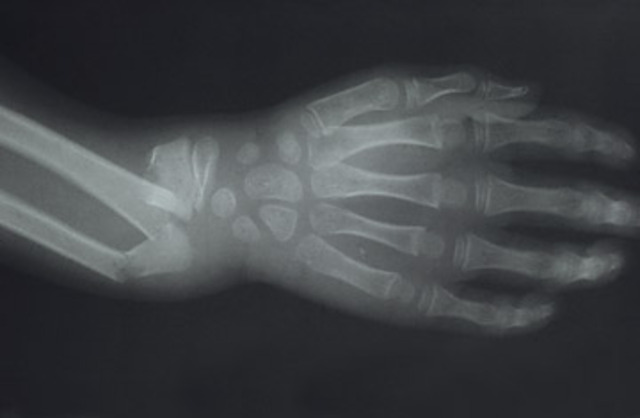

Cuando tenía nueve años yo me rompí mí muñeca. Estaba jugando de fútbol con mi amigo en la lluvia. Entonces yo resbalé mientras corriendo me caí mi muñeca. Yo puse hielo en mi muñeca por un tiempo. Finalmente mi madre me trajo al hospital para x-rays.